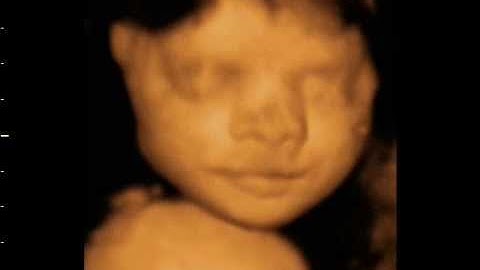

Differences between 2D, 3D 4D and 5D HD Live Ultrasound baby scan. Original Window to the Womb Ltd